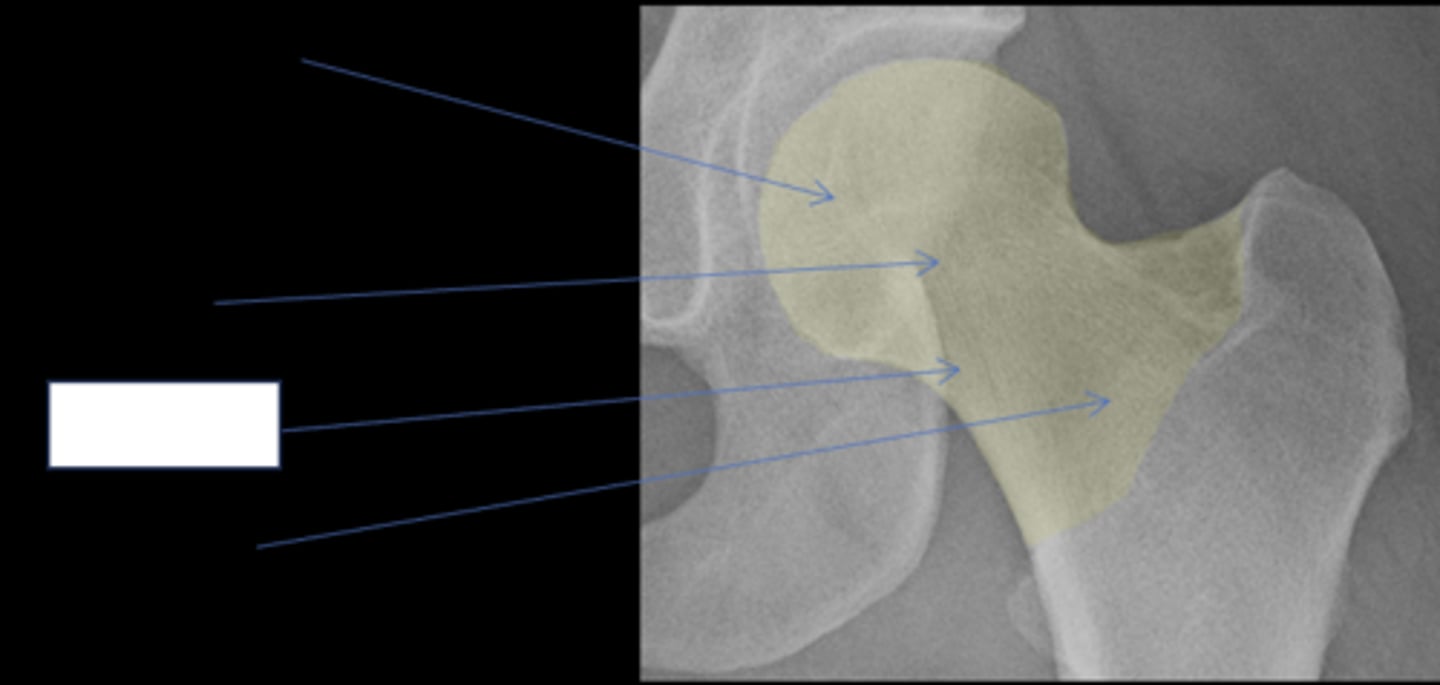

Femoral head

ID anatomy

<p>ID anatomy</p>

16

Subcapital

17

New cards

Mid-cervical

18

Basicervical